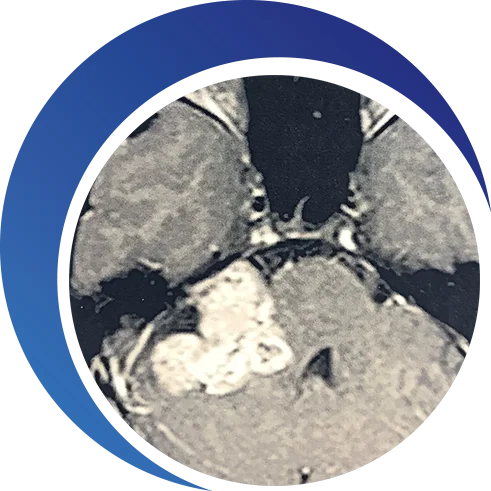

TUMORES EXTENSOS

Um tumor acústico extenso inicia desde o canal ósseo até a cavidade cerebral e é grande o suficiente para produzir pressão no cérebro.